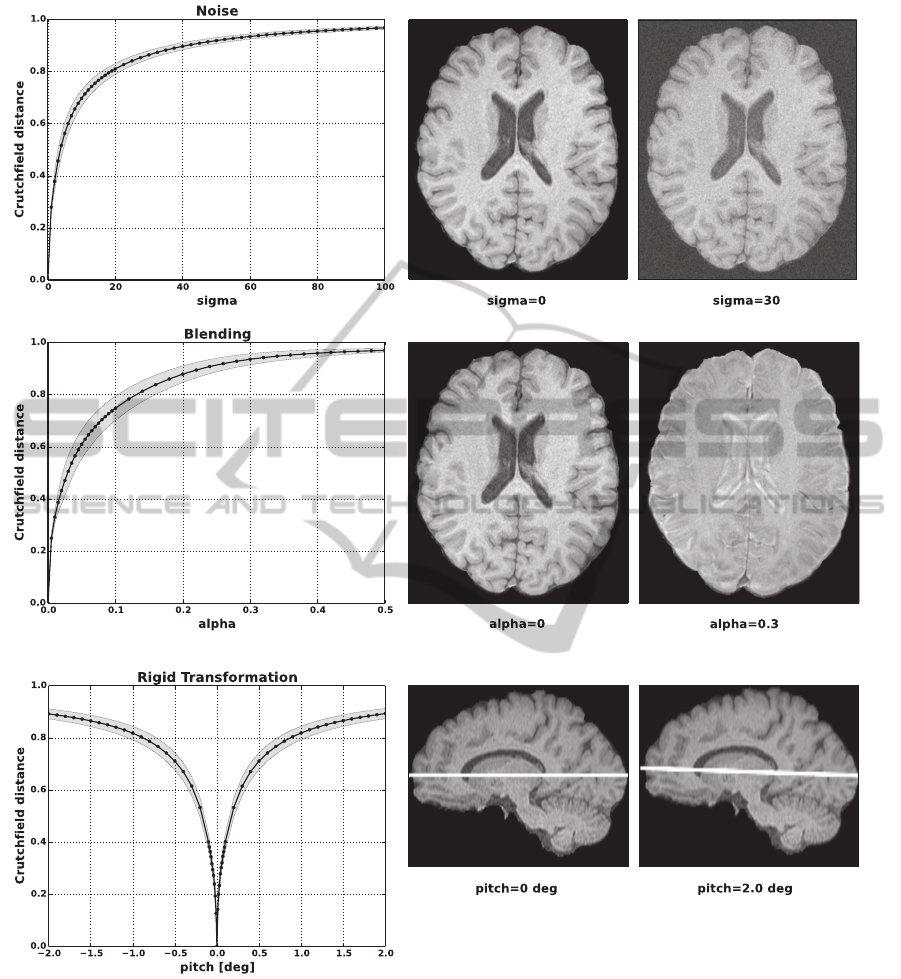

nipulated images by adding noise (Fig. 1A), blending

two MRI sequences (Fig. 1B) and purposefully apply-

ing a rigid transform to them (Fig. 1C). In all cases

the Crutchfield distance increased monotonically with

the amount of manipulation and showed only a small

standard deviation across data set 1 (N = 17). If we